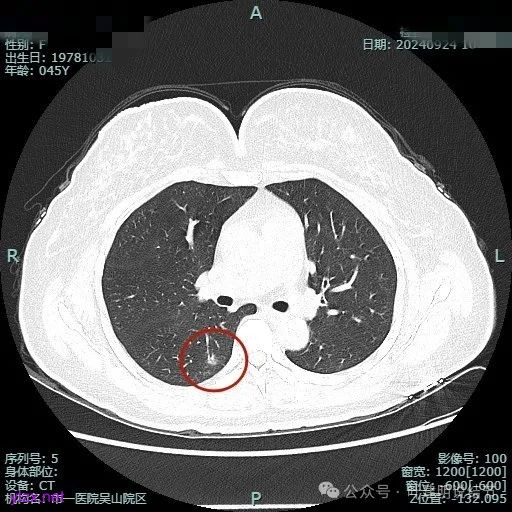

病灶2:

右中叶内侧段可见混合密度结节,大部分实性,形态与下叶背段的类似。